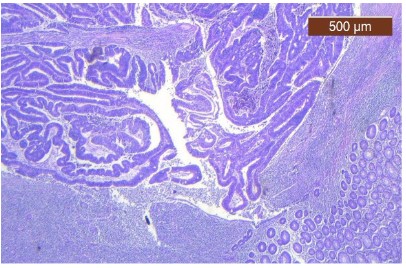

ECG revealed atrial fibrillation with ventricular rate of 80 bpm and anterolateral ischemic changes. Cardiac enzymes were within normal range. The echocardiography indicated hypertensive heart disease, with left ventricular (LV) hypertrophy and diastolic dysfunction, mild left and right atrial enlargement, mild functional mitral and tricuspid regurgitation, systolic LV dysfunction with moderate reduced ejection fraction (EF) 42%, aortic atheromatosis. The thorax-abdomen and pelvic computer tomography (CT) with intravenous and digestive contrast revealed thrombi in the left atrium, mild bilateral pleural effusion, and small hiatus hernia. CT could not identify a lesion suggestive for malignancy, considering also the unsatisfactory bowel preparation. We proceeded the investigations with an inpatient colonoscopy. It revealed a 4-5 cm cauliflower-shaped tumoral mass in the cecum, adjacent to the ileocecal valve (Figure 1). The anatomopathological exam showed papillary and tubular structures with high-grade epithelial dysplasia.

Figure 1: Colonoscopy. Aspect of cauliflower-shaped tumoral mass in the cecum, adjacent to the ileocecal valve.